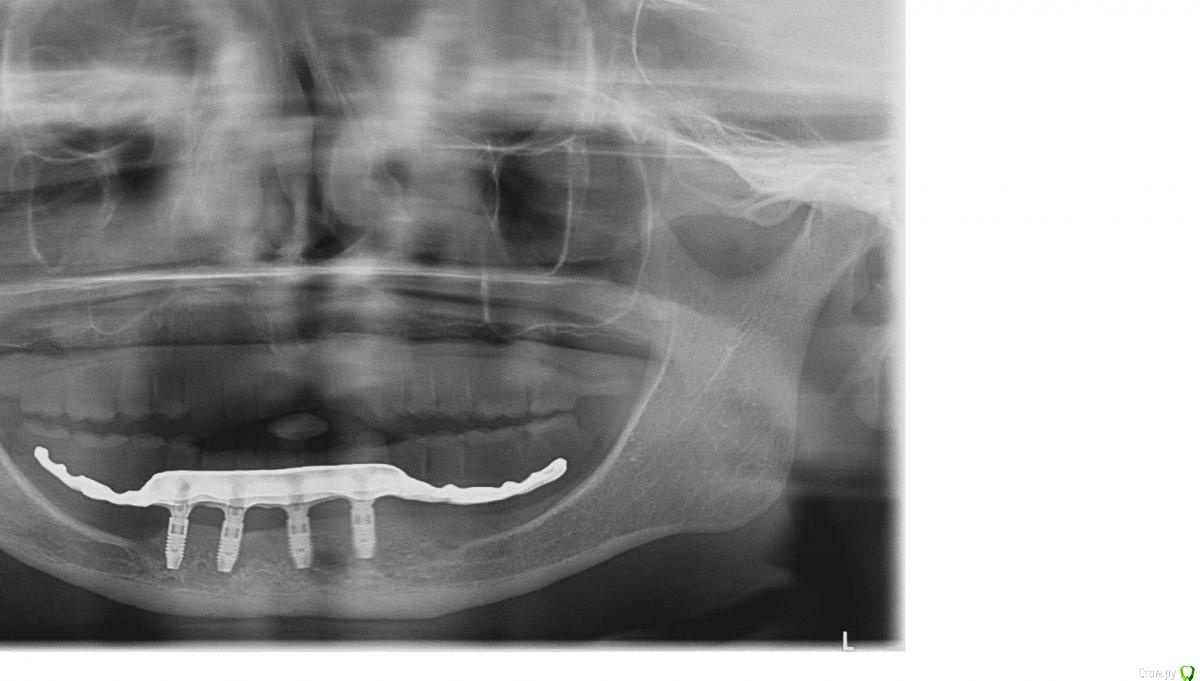

Evikrol Опубликовано 25 ноября, 2016 Поделиться Опубликовано 25 ноября, 2016 В области каких зубов выходят шахты дистальных имплантатов? Ссылка на комментарий

togrul Опубликовано 25 ноября, 2016 Автор Поделиться Опубликовано 25 ноября, 2016 В области каких зубов выходят шахты дистальных имплантато В области каких зубов выходят шахты дистальных имплантатов?Добрый день. в области клыков . снимок на работе Ссылка на комментарий

Aquarius Опубликовано 25 ноября, 2016 Поделиться Опубликовано 25 ноября, 2016 (изменено) Кучно стоят Я стараюсь разнести по саггитали http://s018.radikal.ru/i504/1611/d2/edee533725fa.jpg Изменено 25 ноября, 2016 пользователем Aquarius 4 Ссылка на комментарий

togrul Опубликовано 26 ноября, 2016 Автор Поделиться Опубликовано 26 ноября, 2016 Кучно стоят Я стараюсь разнести по саггитали В данном случае не было условий. Пациентка до этого носила сьемники 15 лет. Ссылка на комментарий

Evikrol Опубликовано 29 ноября, 2016 Поделиться Опубликовано 29 ноября, 2016 Если найдёте скиньте кт. Я уверен что 13 мм войдут Ссылка на комментарий

togrul Опубликовано 29 ноября, 2016 Автор Поделиться Опубликовано 29 ноября, 2016 Если найдёте скиньте кт. Я уверен что 13 мм войдуДаже по панораме видно что там нет 13мм))). Хотите что бы транспозицию сделали ))) под балку Ссылка на комментарий